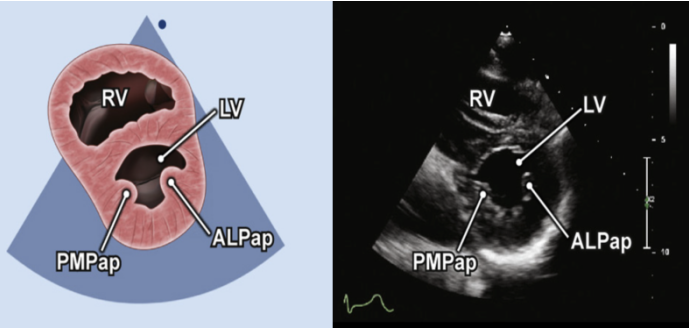

(4)左室短轴切面面积变化分数(LV-FAC%):在胸骨旁短轴(PSAX)乳头肌切面(图24),清晰显示心内膜以后,分别勾勒左室舒张末面积(LVEDA)和左室收缩末面积(LVESA),通过下面公式进行计算:

LV-FAC%=(LVEDA-LVESA)/LVEDA×100%

LVFAC%的参考值为50%~75%。

图片

图24. PSAX乳头肌切面测量LVEA